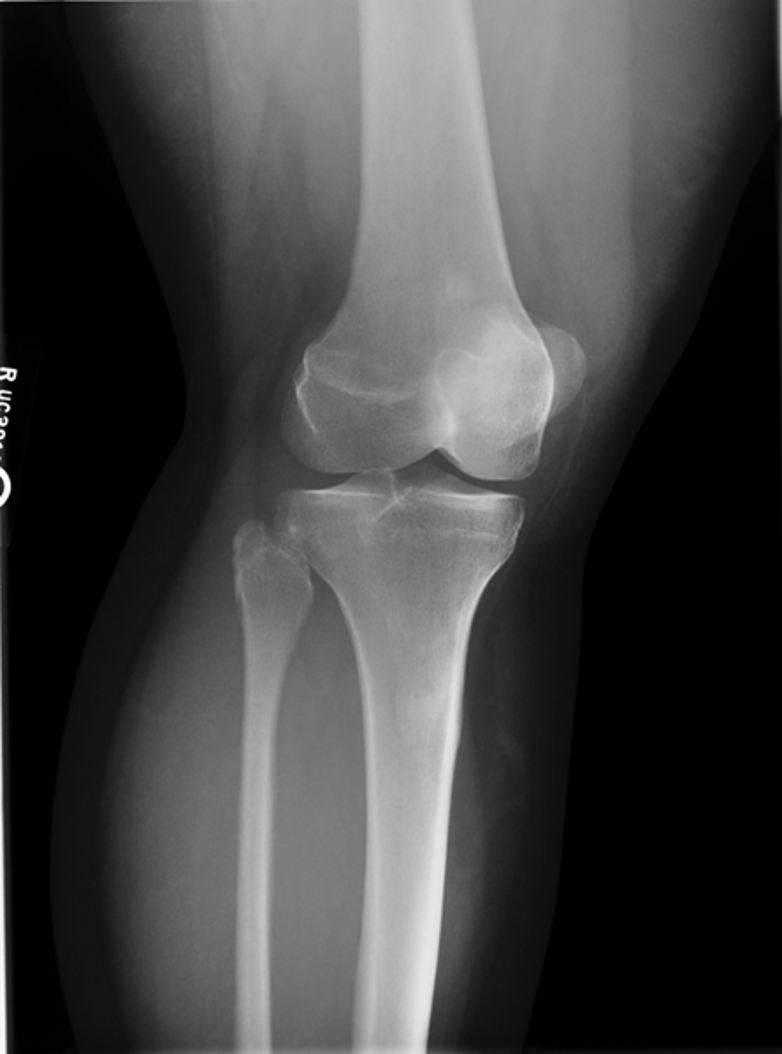

osteoarthritis (degenerative joint disease)

generalized disorder pathologically characterized by loss of joint cartilage & reactive new bone formation

traumatic, stress to joint

what is the casue of osteoarthritis?

advance stage → subtractive disease

pt w/ osteoarthritis

what is this image?